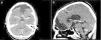

Los schwannomas son neoplasias de la vaina nerviosa originadas de las células de Schwann. Usualmente son solitarios y esporádicos, presentándose en relación a nervios periféricos, espinales o craneales. A nivel intracraneal, presentan una gran predisposición a originarse en el viii par craneal, especialmente en pacientes con neurofibromatosis tipo2. Los schwannomas de la base anterior del cráneo corresponden a menos del 1% del total de schwannomas intracraneanos. Son frecuentes en pacientes jóvenes y usualmente tienen un curso clínico benigno. Estos tumores representan un reto diagnóstico debido a su poca incidencia y sus diagnósticos diferenciales. Se han planteado varias teorías sobre su origen y desarrollo. Se presenta el caso de un paciente varón de 13años sin estigmas clínicos de neurofibromatosis, con un cuadro de cefalea, dolor ocular, papiledema y disminución de la agudeza visual en el cual se documentó un tumor único ubicado en la fosa craneal anterior. Se realizó una resección completa de la masa tumoral, cuyo diagnóstico histopatológico fue de schwannoma, y presentó una recuperación clínica de todos sus síntomas. En una revisión bibliográfica se ubicó un total de 66 pacientes reportados a nivel mundial con este diagnóstico. Se describen sus características epidemiológicas y clínicas más relevantes, así como la relación con los tumores de las células de la vaina olfatoria, una entidad descrita recientemente y que presenta gran similitud.

Schwannomas are nerve sheath tumours that originate in Schwann cells. They are usually solitary and sporadic and manifest on peripheral, spinal or cranial nerves. Intracranial schwannomas tend to manifest on the eighth cranial nerve, particularly in patients with neurofibromatosis type2. Anterior skull-base schwannomas represent less than 1% of all intracranial schwannomas. They are more frequent in young people and are typically benign. These tumours represent a diagnostic challenge due to their rarity and difficult differential diagnosis, and numerous theories have been postulated concerning their origin and development. In this article, we present the case of a 13-year-old male with a single anterior cranial-base tumour not associated with neurofibromatosis who presented with headache, papilloedema, eye pain and loss of visual acuity. Complete resection of the tumour was performed, which was histopathologically diagnosed as a schwannoma. The patient made a complete clinical recovery with abatement of all symptoms. We conducted a review of the literature and found 66 cases worldwide with this diagnosis. We describe the most relevant epidemiological and clinical characteristics of this kind of tumour and its relation with the recently discovered and similar olfactory schwannoma.